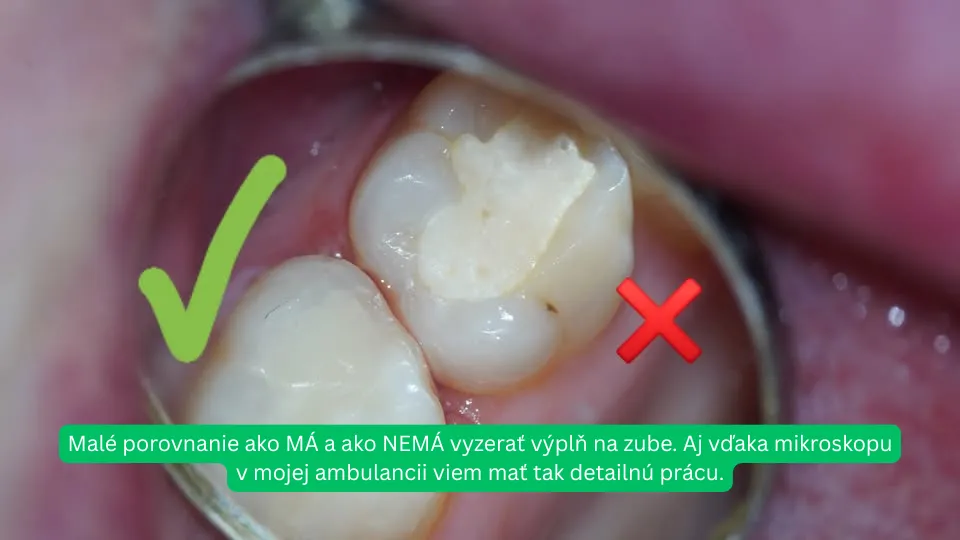

Vysokoškolské štúdium ukončila v roku 2014 na Lekárskej fakulte Univerzity Pavla Jozefa Šafárika v Košiciach. Vo svojej praxi sa zameriava na preventívnu, detskú a záchovnú stomatológiu, endodonciu, protetiku a dentálnu hygienu. Pri svojej práci využíva stomatologické lupy a dentálny mikroskop, vďaka čomu sa dokáže sústrediť aj na tie najmenšie detaily a dosahovať vysokú presnosť ošetrení. Pravidelne, každoročne absolvuje teoretické aj praktické odborné školenia, ktoré ju posúvajú vpred a umožňujú jej aplikovať moderné postupy v každodennej praxi.

V našej ambulancii kladieme dôraz na presnosť, šetrnosť a dlhodobý výsledok. Preto pri mnohých zákrokoch využívame zubný mikroskop a dentálne lupy. Umožňuje nám to pracovať v niekoľkonásobnom zväčšení – až do 25-násobku bežného pohľadu.

Kvalitná stomatológia nie je len o rukách, ale aj o tom, čo vidíme. S mikroskopom vidíme viac – a vy máte istotu, že vaše zuby sú v tých najlepších rukách.